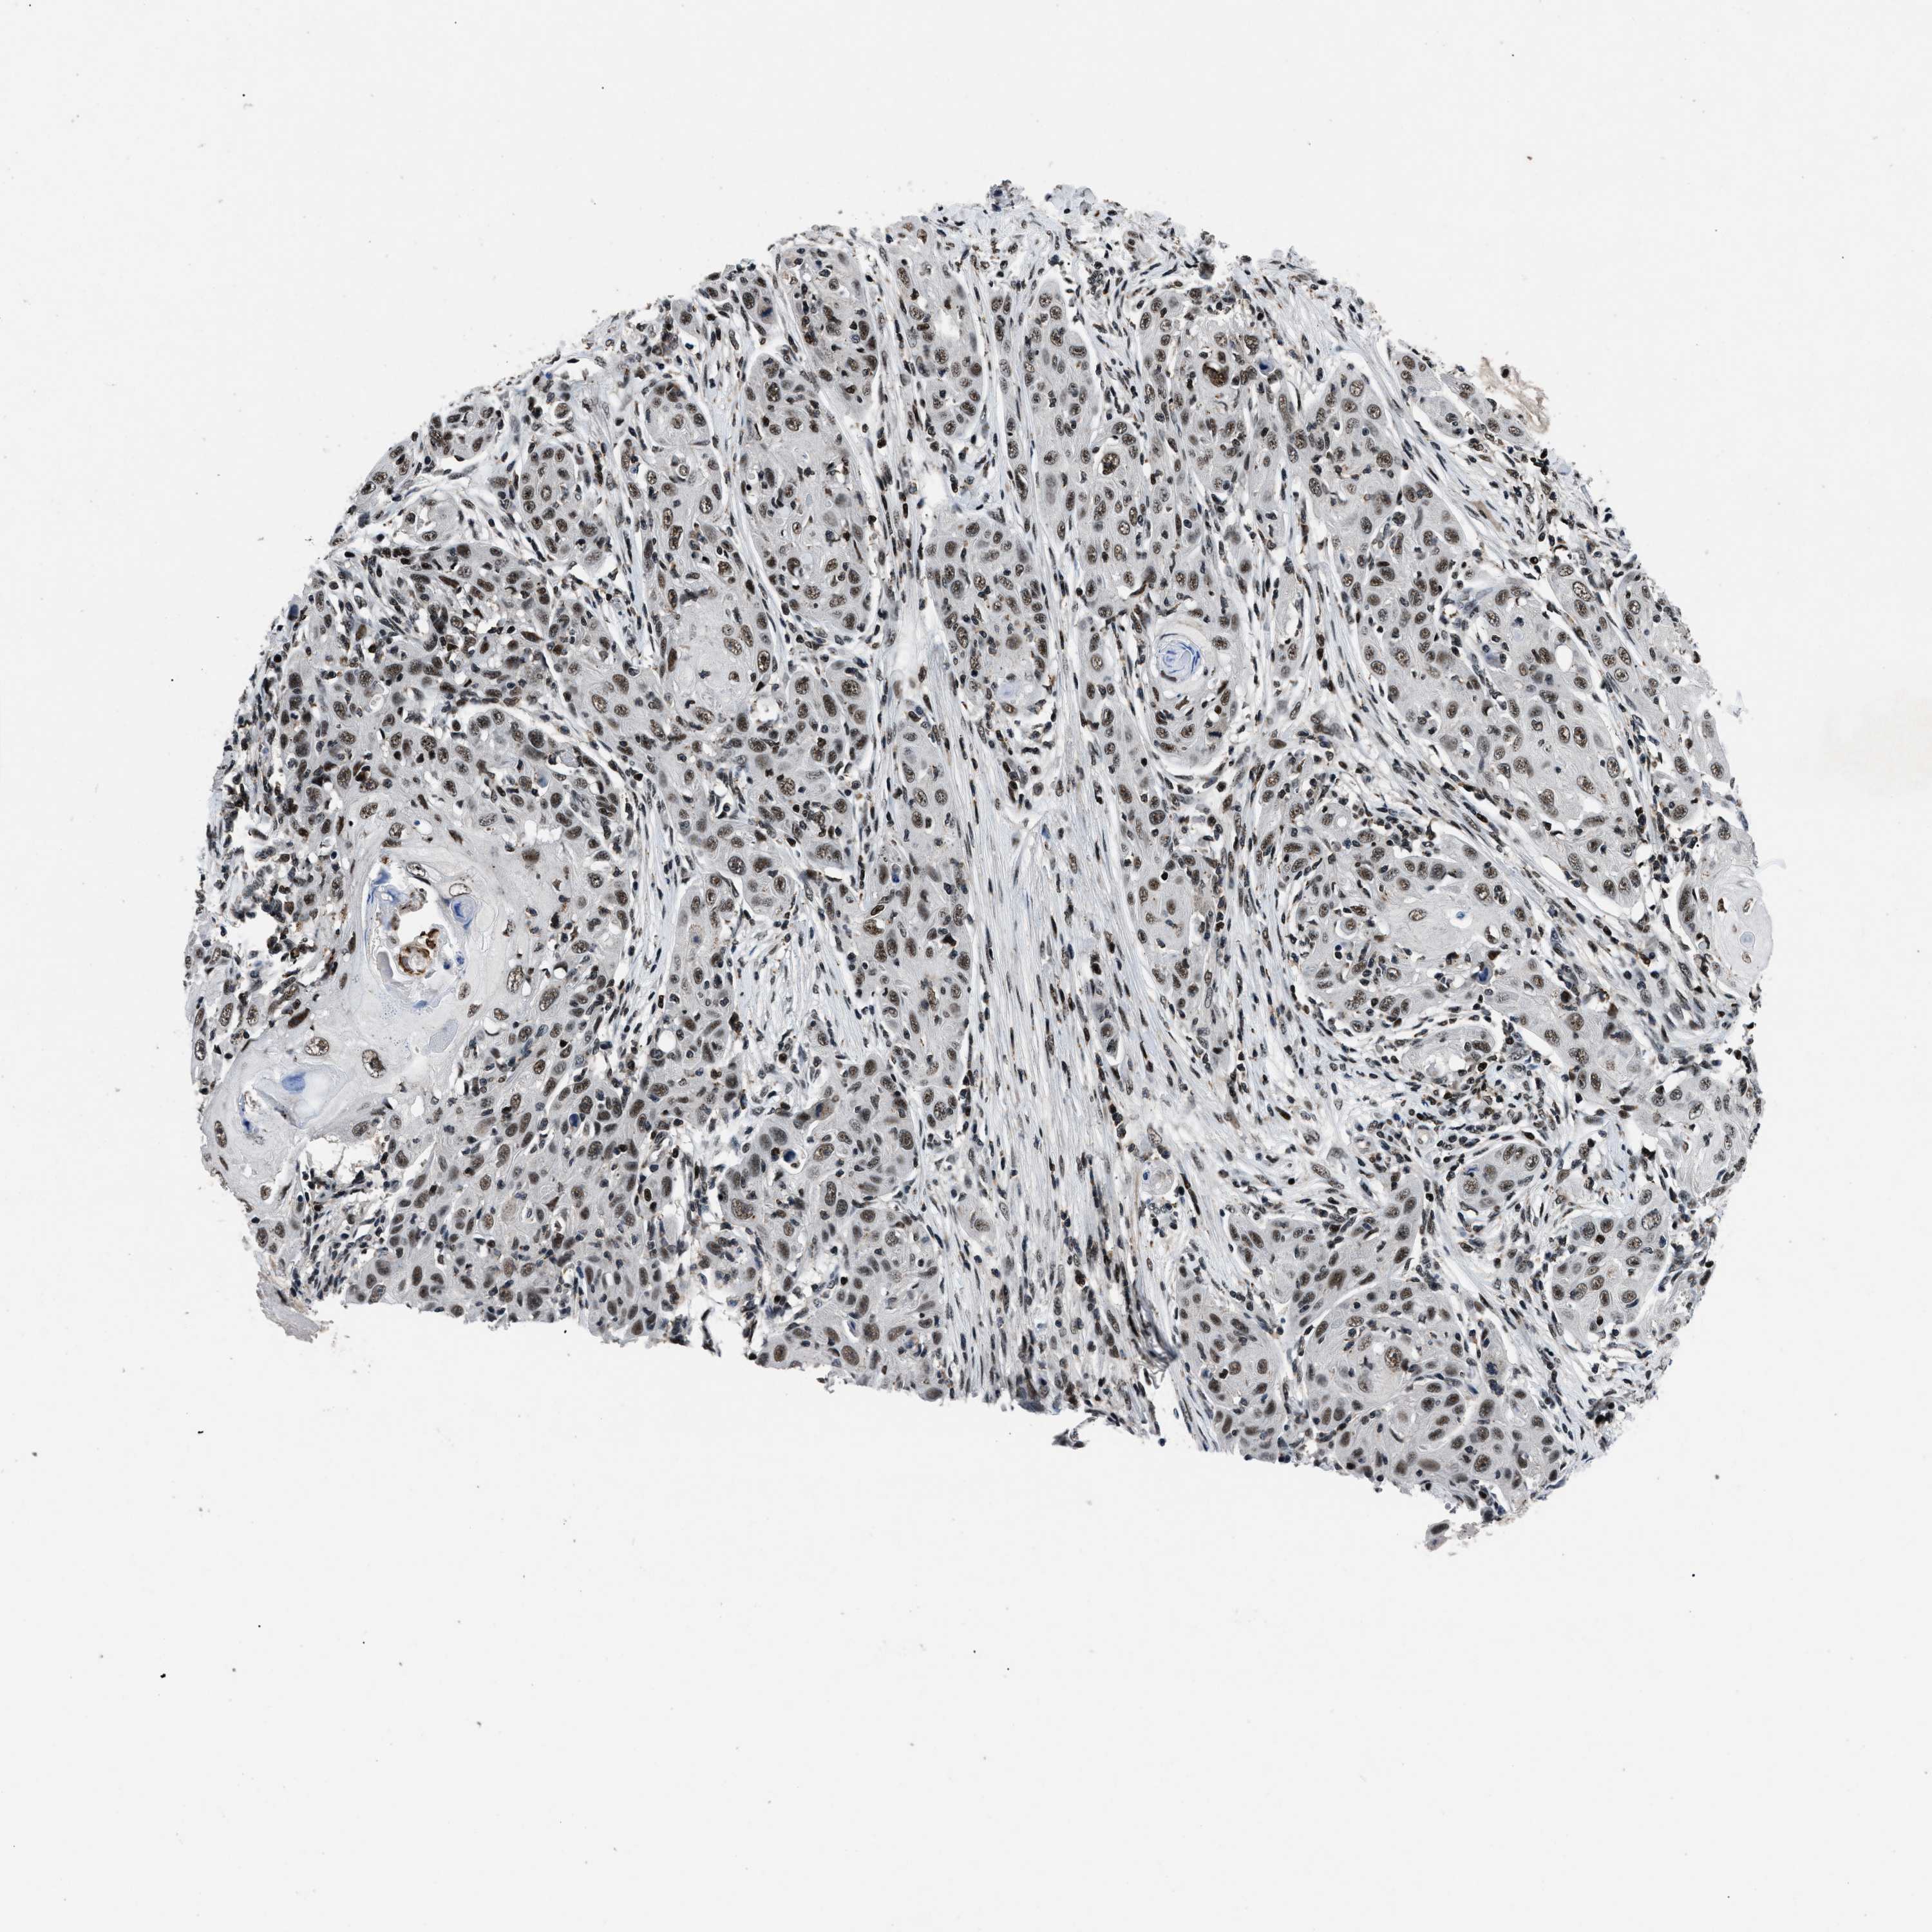

SKIN CANCER - Protein expressioni

A mouse-over function shows sample information and annotation data. Click on an image to view it in a full screen mode. Samples can be filtered based on level of antibody staining by selecting one or several of the following categories: high, medium, low and not detected. The assay and annotation is described here.

Antibody staining in the annotated cell types in the current human tissue is reported as not detected, low, medium, or high, based on conventional immunohistochemistry profiling in selected tissues. This score is based on the combination of the staining intensity and fraction of stained cells.

Each image is clickable and will lead to virtual microscopy that enables deeper exploration of all samples and also displays staining intensity scores, fraction scores and subcellular localization as well as patient and tissue information for each sample.

Antibody HPA019127

Staining

High

Strong

>75%

Location

Basal cell carcinoma